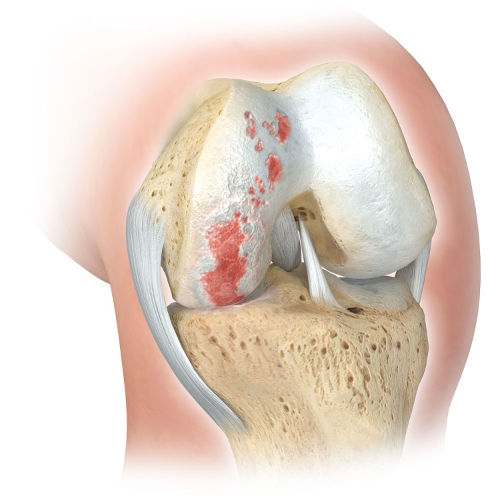

εικ. Εκφυλιστική φθορά (αρθρίτιδα) του αρθρικού χόνδρου μόνο στην έσω πλευρά του γόνατος (αριστερό τμήμα της εικόνας).

Το έξω τμήμα του γόνατος είναι υγιές (δεξί τμήμα της εικόνας)